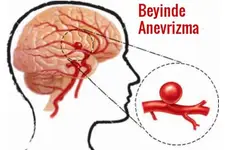

Beyinde kitle ameliyatı, genellikle tümörler, kist veya diğer anormal oluşumların cerrahi olarak çıkarılması amacıyla yapılan bir işlemdir. Bu tür bir ameliyat, beyin dokusuna doğrudan müdahale gerektiği için belirli riskler taşır ve sonrasında hastalar için çeşitli zorluklar ortaya çıkabilir. İşte bu makalede, beyin kitle ameliyatının riskleri ve sonrası hakkında detaylı bir inceleme yapılacaktır. 1. Beyin Kitle Ameliyatının Riskleri Beyin kitle ameliyatı, birçok risk barındırır. Bu riskler arasında şunlar bulunmaktadır:

4. Potansiyel Komplikasyonlar Ameliyat sonrası komplikasyonlar, hastanın genel sağlığını etkileyebilir. Bunlar arasında: